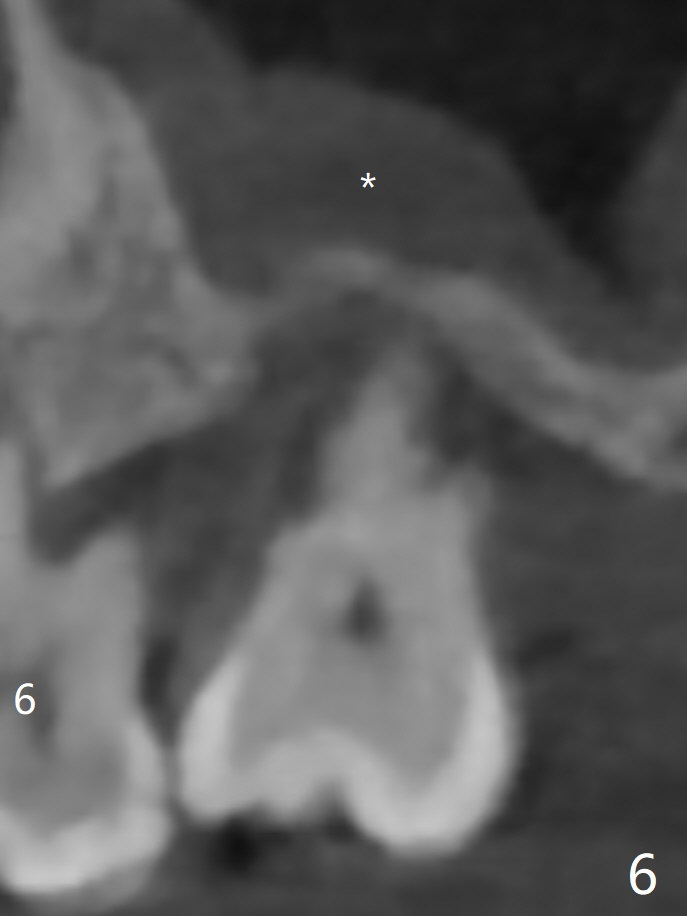

45岁女右上7严重骨质吸收终于开始出现症状(图一),虽然邻牙(6)骨质吸收也明显(图二,四,六,八,十),但是保留它,远中颊侧(DB),腭侧(P)根成为骨粉(图三,五,七,九,十一:红圆圈)支架。